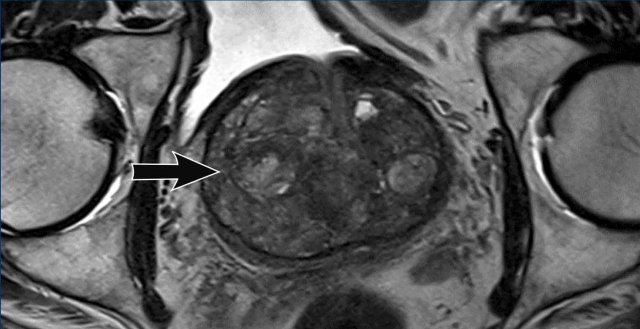

Prostate cancer in PZ

For the peripheral zone the DWI/ADC is the primary determining sequence to assign the PI-RADS assessment category.

First look at the images and describe what you see.

A 16 mm lesion (measurement not

shown) was detected and located dorsally in the peripheral zone of the

mid-portion of the prostate on the right.

This lesion was assigned to PI-RADS

category 5, based on marked hypointensity on ADC and marked hyperintensity on

DWI (score 5 - dominant sequence), correlated to markedly hypointensity on T2W

(score 5).

The Gleason score was 3+4, which

means intermediate risk of an aggressive cancer.

The lesion does not abut the

pseudocapsule and there is no sign of extraprostatic growth.